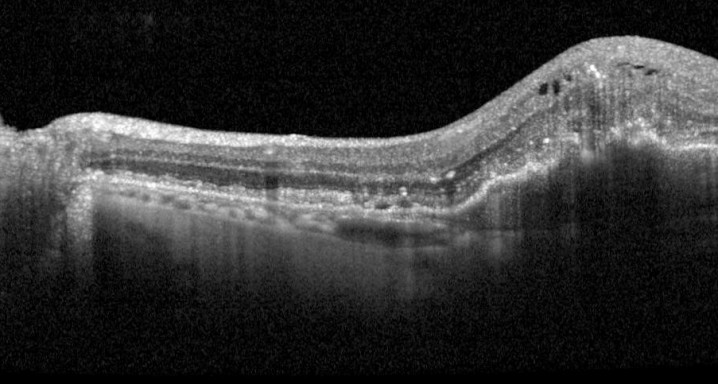

Este estudio evaluará la seguridad y la tolerabilidad a largo plazo de Faricimab intravitrio en pacientes con degeneración macular neovascular relacionada con la edad (nAMD) que hayan completado cualquiera de los estudios de Fase III (GR40306 o GR40844). Se realizarán evaluaciones adicionales relacionadas con la eficacia, la farmacocinética, la inmunogenicidad y los biomarcadores.

Faricimab es el primer fármaco biespecifico de uso intraocular que inhibe dos vías de acción de la enfermedad neutralizando la angiopoietina-2 (Ang-2) y el factor de crecimiento endotelial vascular-A (VEGF-A)

DMAE seca o atrófica